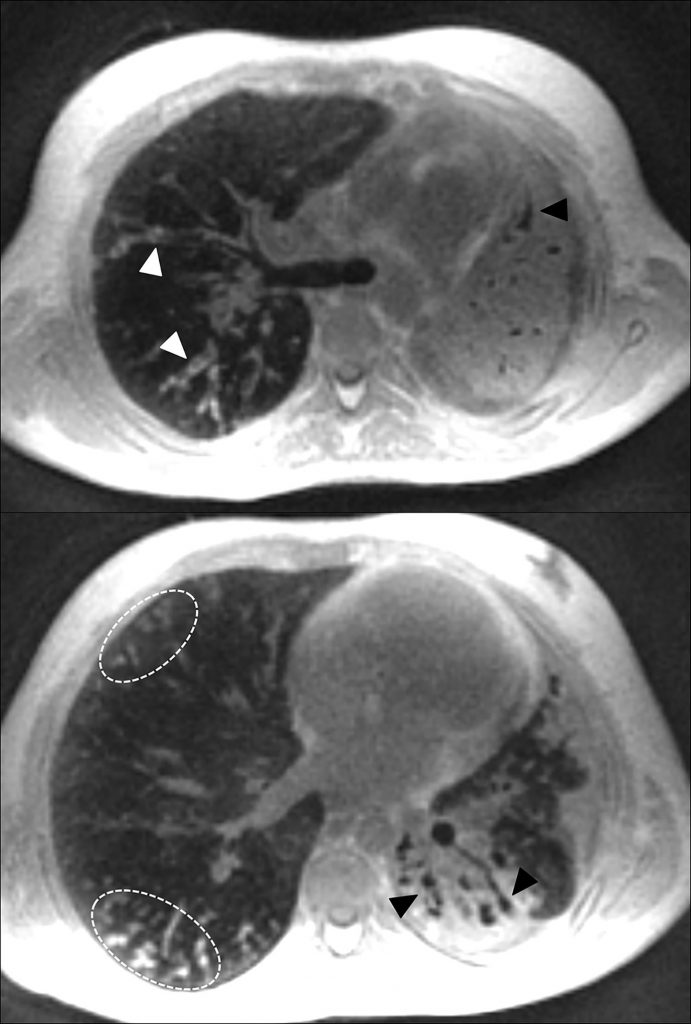

En IRM, des protocoles incluant les nouvelles séquences tridimensionnelles à temps d’écho ultracourt (figure 125.3) et les séquences synchronisées à la respiration sont à l’étude comme alternative non irradiante à la TDM.

Fig. 125.3 IRM pulmonaire sans injection : séquence à zéro temps d’écho (ZTE).

Dilatations des bronches cylindriques à parois épaisses (flèches blanches), condensation apico-dorsale du lobe supérieur et du segment apical du lobe inférieur à gauche, contenant des dilatations des bronches (flèches noires), impactions mucoïdes distales dans le lobe moyen et le segment apical du lobe inférieur droit (pointillés blancs).

Source : CERF, CNEBMN, 2022.